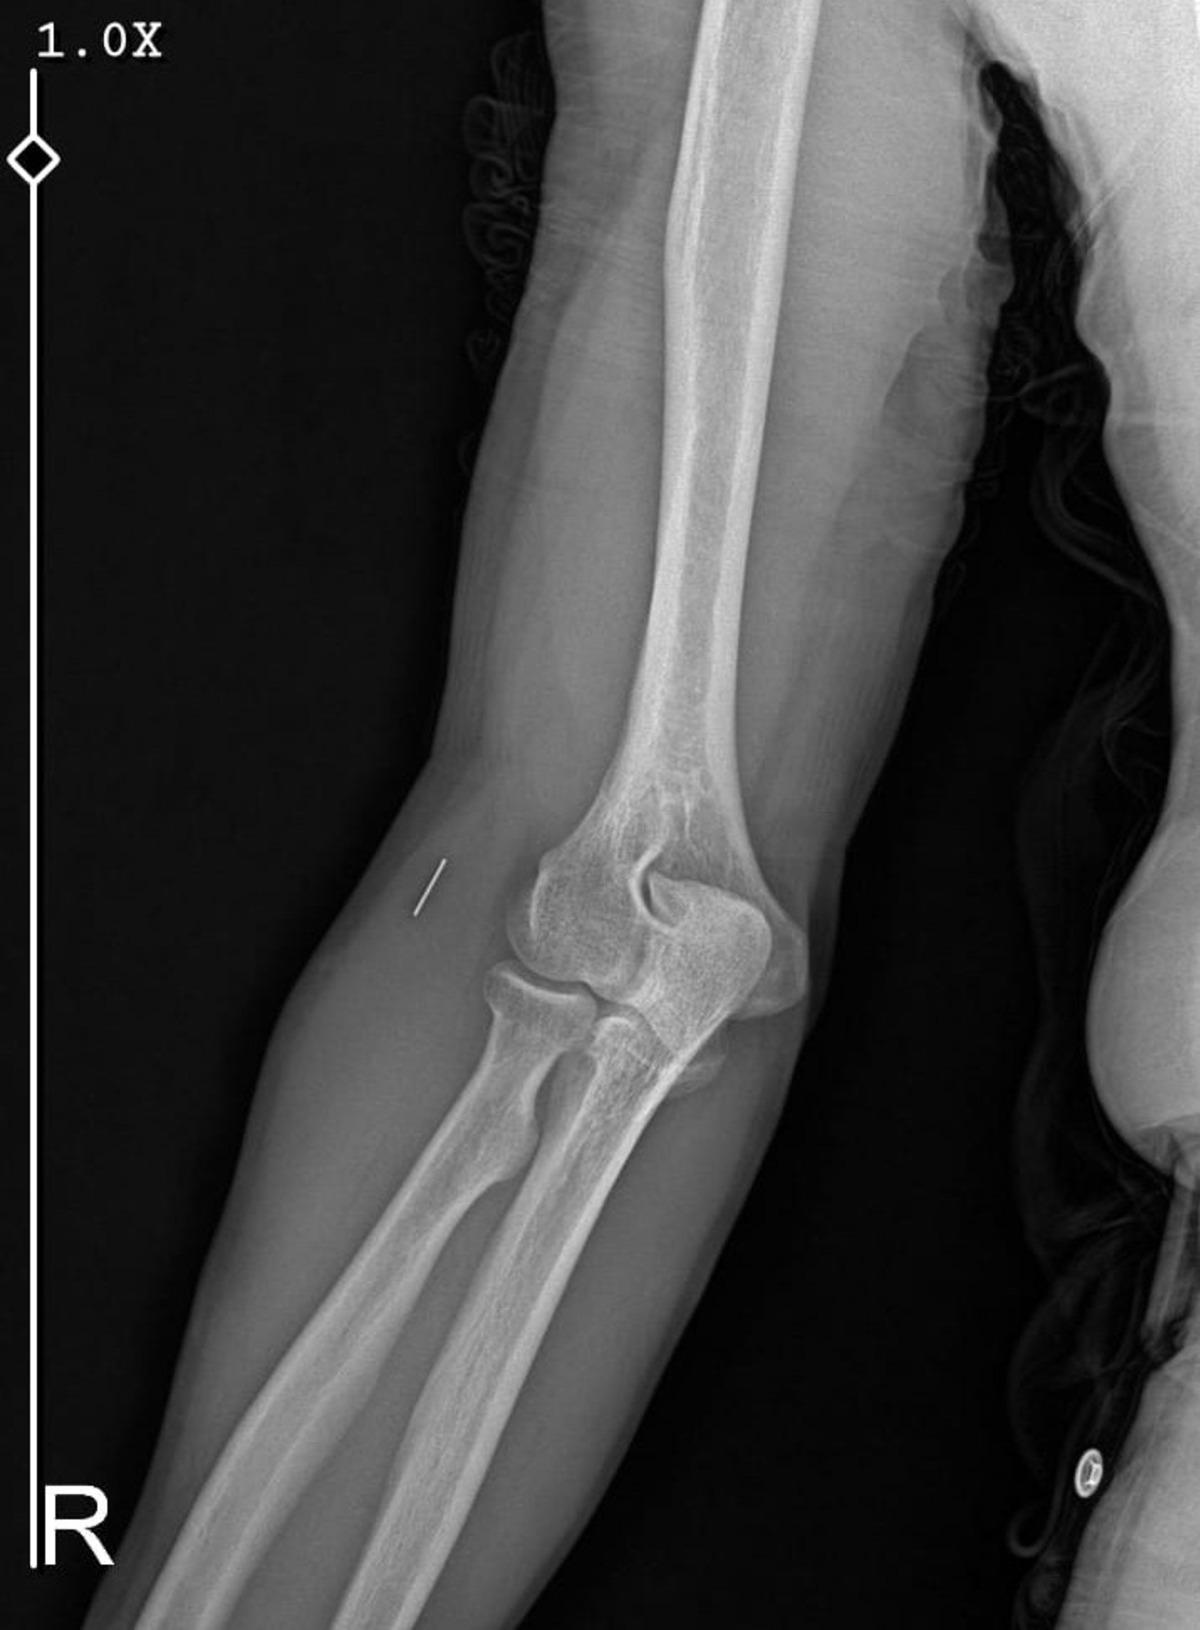

Öte yandan, ameliyatların ardından ağrıları devam eden Güleryüz'ün kolunda metal parça bulunduğu ve bu parçanın parmak bölgesinden dirseğe doğru ilerlediği öne sürüldü. Ayrıca, fabrikada temizlik personeli olarak çalışan Nurettin Güleryüz'ün hastane sürecinde işten çıkarıldığı da öğrenildi.

"Doktorlara bileğime doğru ağrılarım olduğunu sürekli ifade etmeme rağmen beni dinlemediler. Sonradan kolumda metal kaldığını öğrendik. Bunun ihmal olduğunu düşünüyoruz. Çünkü kola metal nasıl girebilir? Ben 9 aydır çalışamıyorum. Kalp rahatsızlığım sebebiyle yüzde 46 engelliyken şu anda yüzde 75 engelli durumuna düştüm. Erken emeklilik dilekçesi verdim ancak henüz sonuç gelmedi. Bu konuda çok mağdurum. Yetkililerin bunu duymasını istiyorum. Savcılığa suç duyurusunda bulunduk. Yaklaşık 9 aydır henüz soruşturma izni gelmedi. Süreci bekliyoruz, henüz dava açılmış değil. Kolumda bırakılan metal ilerliyor. Pazartesi günü bunun için de operasyon geçireceğim. Çıkarılıp çıkarılamayacağı net değil. Elimde titremelerim var, çalışamıyorum ve işveren tarafından işten çıkarıldım. Yetkililerden destek ve konunun incelenmesini talep ediyorum."